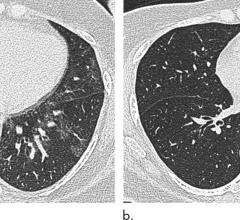

February 5, 2020 — In a special report published in the journal Radiology, researchers describe computed tomography (CT) ...

January 28, 2020 — Pulmonary imaging is important in the diagnosis of the acute lung injury associated with vaping ...